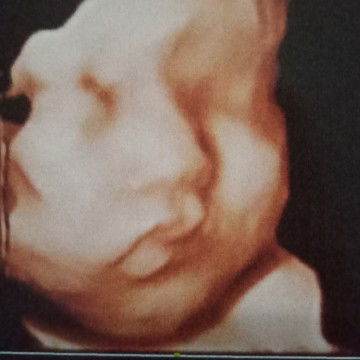

Alhamdulillah

Alhamdulillah,walaupun kmren Smpet jatuh kepleset....tpi smua sehat,dan tdk krang suatu apapun....anak mama yg kuat,,,bahagia'ya ga bsa d'ungkapkan...